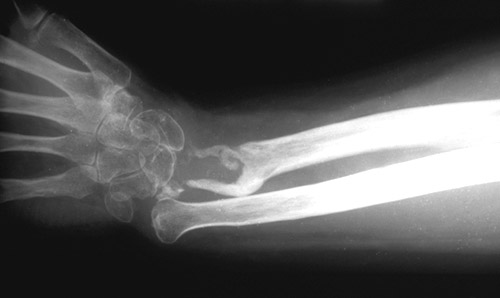

The lytic region (GCT) of the radial head seen with this radiograph proved to be a giant cell tumor of bone. These neoplasms arise in the epiphyseal region of long bones, and sometimes the axial skeleton.